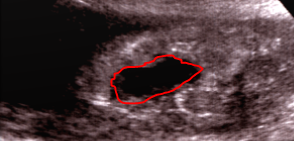

"Dans les formes graves, elle [l'échographie] ne peut que confirmer, la mort foetale et apprécier le volume du caillot (pas toujours facile à voir à l’échographie) :

il se manifeste par une zone anéchogène retroplacentaire."

:arrow: la zone anéchogène se situe derrière le placenta (c'est un liquide ici du sang) et elle est noire

anéchogène.PNG

anéchogène.PNG (76.4 Kio) Vu 331 fois

"Dans les formes moins importante, le diagnostic peut être difficile à différencier du placenta (il est plus échogène)."

:arrow: la zone est plus blanche et ne se différencie pas avec l'échogénicité du placenta, l'HRP va former un caillot donc sera solide et de ce fait plus echogène :)